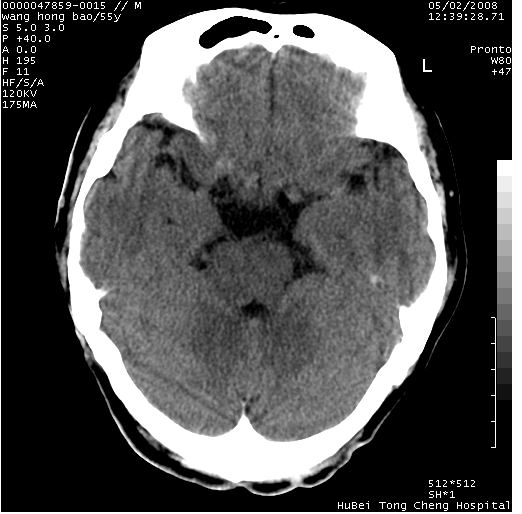

以下是引用dyqct在2008-5-3 23:36:00的发言:[br]桥前池区可疑蛛网膜囊肿。其它未见明显异常。建议做mri。

以下是引用zjzjr在2008-5-4 14:50:00的发言:[br]桥前池区可疑蛛网膜囊肿。其它未见明显异常。建议做mri。